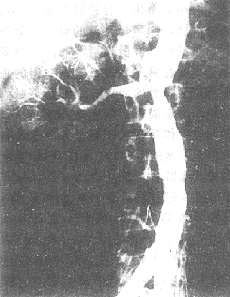

3、腎影像學檢查

多採用腹平片、超音波、CT、磁共振等檢查有助於了解腎臟的大小、形態、血管及輸尿管、膀胱有無梗阻、也可了解腎血流量、腎炎效果球和腎小管的功能,使用造影劑可能加重腎損害,須慎用。

(2)腎後性ARF:泌尿系統影像學檢查有助於發現導致尿路梗阻的病因。